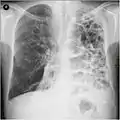

قد يفيد تصوير الصدر بالأشعة السينية والعد الدموي الشامل في استبعاد أسباب أخرى في وقت التشخيص.[58] والسمات المميزة للأشعة السينية هي التمدد الشديد للرئتين، وانبساط الحجاب الحاجز، وزيادة حيز الهواء خلف القص، والأمراض الجلدية، في حين أنها قد تساعد في استبعاد أمراض الرئة الأخرى مثل ذات الرئة ووذمة الرئة أو الاسترواح الصدري.[59] يمكن لصورة الصدر عالية الوضوح باستخدام التصوير المقطعي المحوسب بالأشعة السينية أن تبين توزيع النفاخ الرئوي في جميع أنحاء الرئتين ويمكن أيضاً أن تكون مفيدة في استبعاد أمراض الرئة الأخرى.[17] إذا لم يكن مخططاً لإجراء عملية جراحية، فهذا نادراً ما يؤثر على العلاج.[17] ويتم استخدام غازات الدم الشرياني لتحديد مدى الحاجة إلى الأكسجين؛ ويوصى به لمن يُتوقع أن يكون حجم الزفير القسري لديهم1 أقل من 35%، والذين لديهم تشبع أكسجين محيطي أقل من 92% والذين تظهر لديهم أعراض قصور القلب الاحتقاني.[16] في مناطق العالم التي يشيع فيها نقص مضاد التريبسين ألفا-1، يجب أن يوضع في الاعتبار اختبار الأشخاص المصابين بمرض الانسداد الرئوي المزمن (خاصة من هم دون سن 45 ولديهم نفاخ رئوي يؤثر على الأجزاء السفلية من الرئتين).[16]

صورة الأشعة السينية تبين حالة شديدة من الانسداد الرئوي المزمن. لاحظ صغر حجم القلب مقارنة بالرئتين.